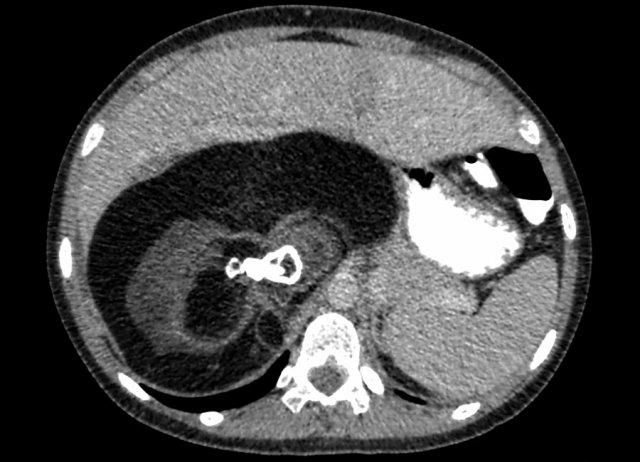

Hình ảnh

U nguyên bào thận ở thận trái của bé trai ba tuổi. Phần còn lại của thận trải dài trên khối u (dấu hiệu “móng vuốt” mũi tên). Khối u khá đồng nhất với một số vùng nang.

Siêu âm

Hình ảnh ban đầu thường được thực hiện bằng siêu âm. Các khối u nhỏ hơn sẽ được thấy di chuyển đồng bộ với thận. Các khối u lớn sẽ không di chuyển.

Như đã đề cập trước đó, thường có thể phát hiện phần nhu mô thận còn lại bao quanh khối u, được gọi là dấu hiệu móng vuốt. Phần nhu mô còn lại có thể có đài thận giãn do tắc nghẽn bể thận.